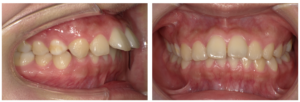

上顎前突の治療(インビザライン マウスピース矯正)

治療前

治療後

| 主訴 | 19歳女性 上の前歯が気になる |

| 治療期間 | 1年6ヶ月 |

| 治療費 | 80万5000円+税 |

| 治療内容 | インビザラインで矯正治療を行った。上の奥歯を後ろに移動させる動きと、隣接面の削合によりスペースを獲得し、奥歯の噛み合わせを改善しながら、前歯の突出感を解消した。 |

| 治療のリスク | マウスピースを規定の時間使用しないと、予定通りに治療を進めることが困難になり、治療期間が延長する。奥歯が予定通りに移動しない場合は、隣接面削合の量が増加する。 |